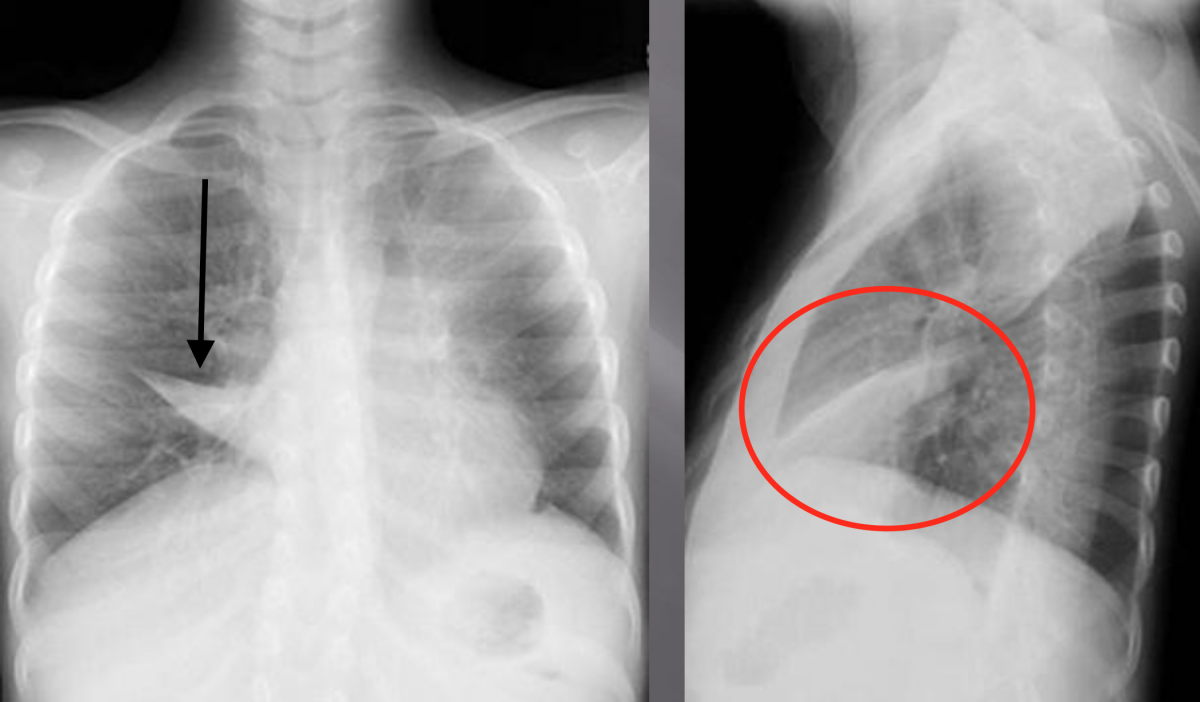

Рентгеновские снимки при врожденной эмфиземе легкого

Раздел: Визуальные уроки